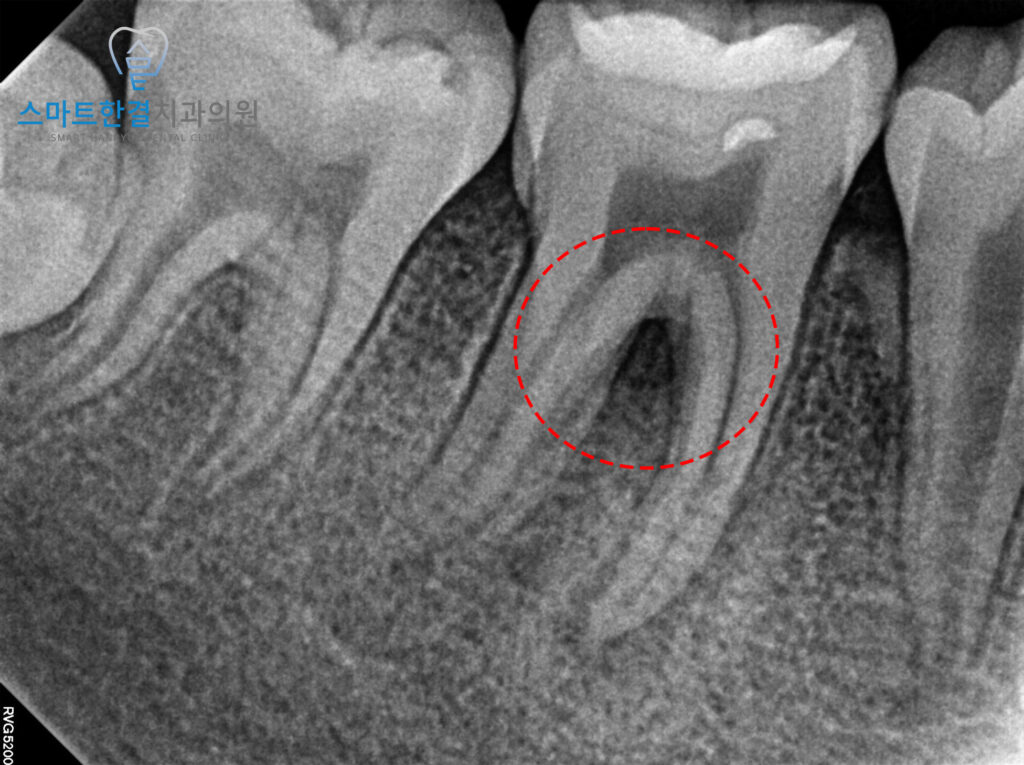

정밀한 엑스레이 사진을 촬영해본 결과,

염증이 뚜렷하게 나타났으며

치아 뿌리 주변으로 염증이 확산된 상태임을

확인할 수 있었어요.

치수생활력이 상실되어 있어,

치아의 뿌리가 제대로 성장하지

못했을 가능성이 있었는데요.

이에 화서동치과 스마트한결에서는

신경치료를 위해 신경이 있는 공간을 열어

상태를 확인해보기로 하였답니다!